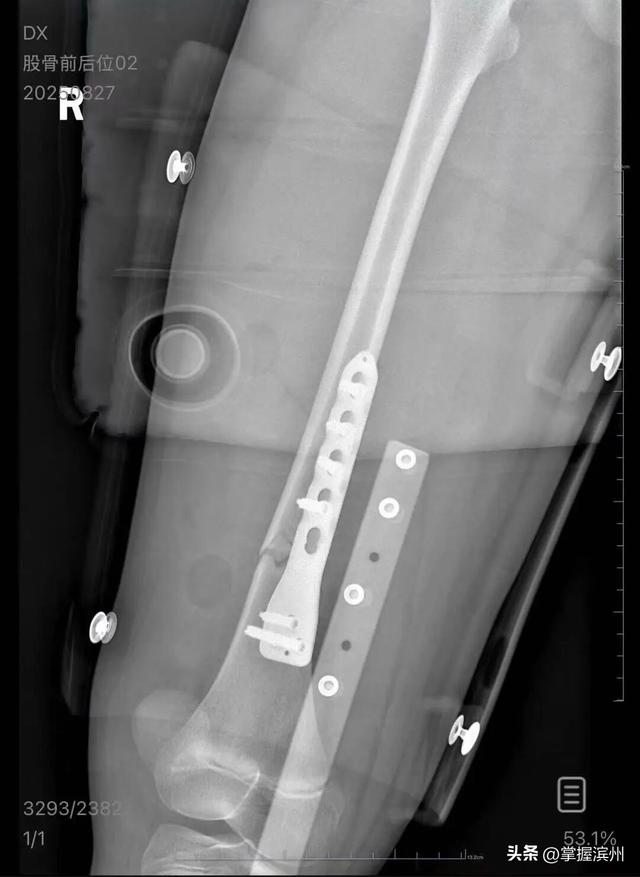

▲朱女士女儿手术后拍的X光片 受访者供图

朱女士向记者出示的医院病历显示,8月24日凌晨,朱女士的女儿到医院就诊。医院诊断朱女士的女儿右股骨骨折 ,需要住院进一步治疗 。

朱女士告诉扬子晚报/紫牛新闻记者,医疗费加上护工费已经花费了5万多元 ,“而且在出院以后 ,医生说因为植入了钢板,后续孩子可能会有后遗症,最有可能出现的是长短腿 ,让我们去做康复治疗,这就面临着另一笔费用 。 ”